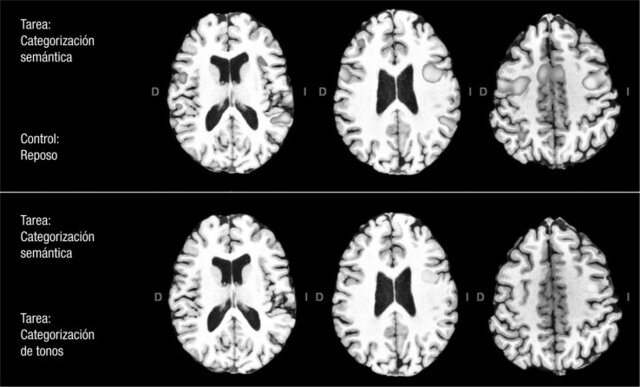

• Implementación de imágenes

Implementación de imágenes

En la década de los 90 se consolida la investigación con la implementación de imágenes que dejaron de ser anatómicas para empezar hacer funcionales.